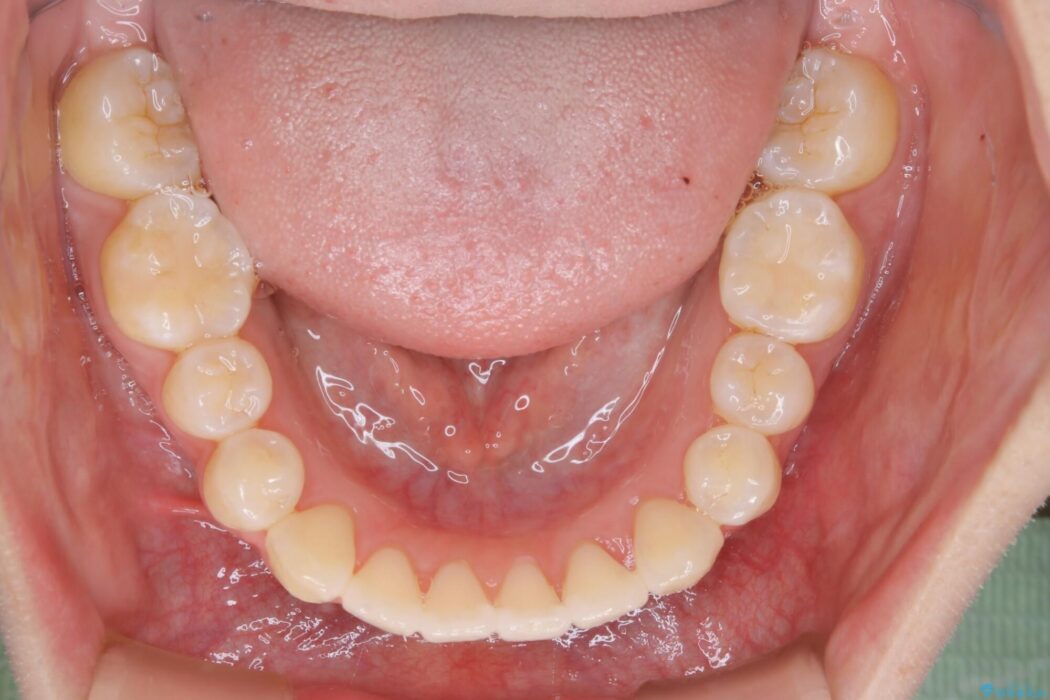

治療前と治療後を見比べると口元の見た目の変化が良く分かります。

本症例では奥歯から順に移動させるため前歯の変化を感じるには時間が掛かりましたが、インビザライン装置とマイクロインプラントを併用することで健康な歯を抜歯することなく歯列をきれいに整えることができました。